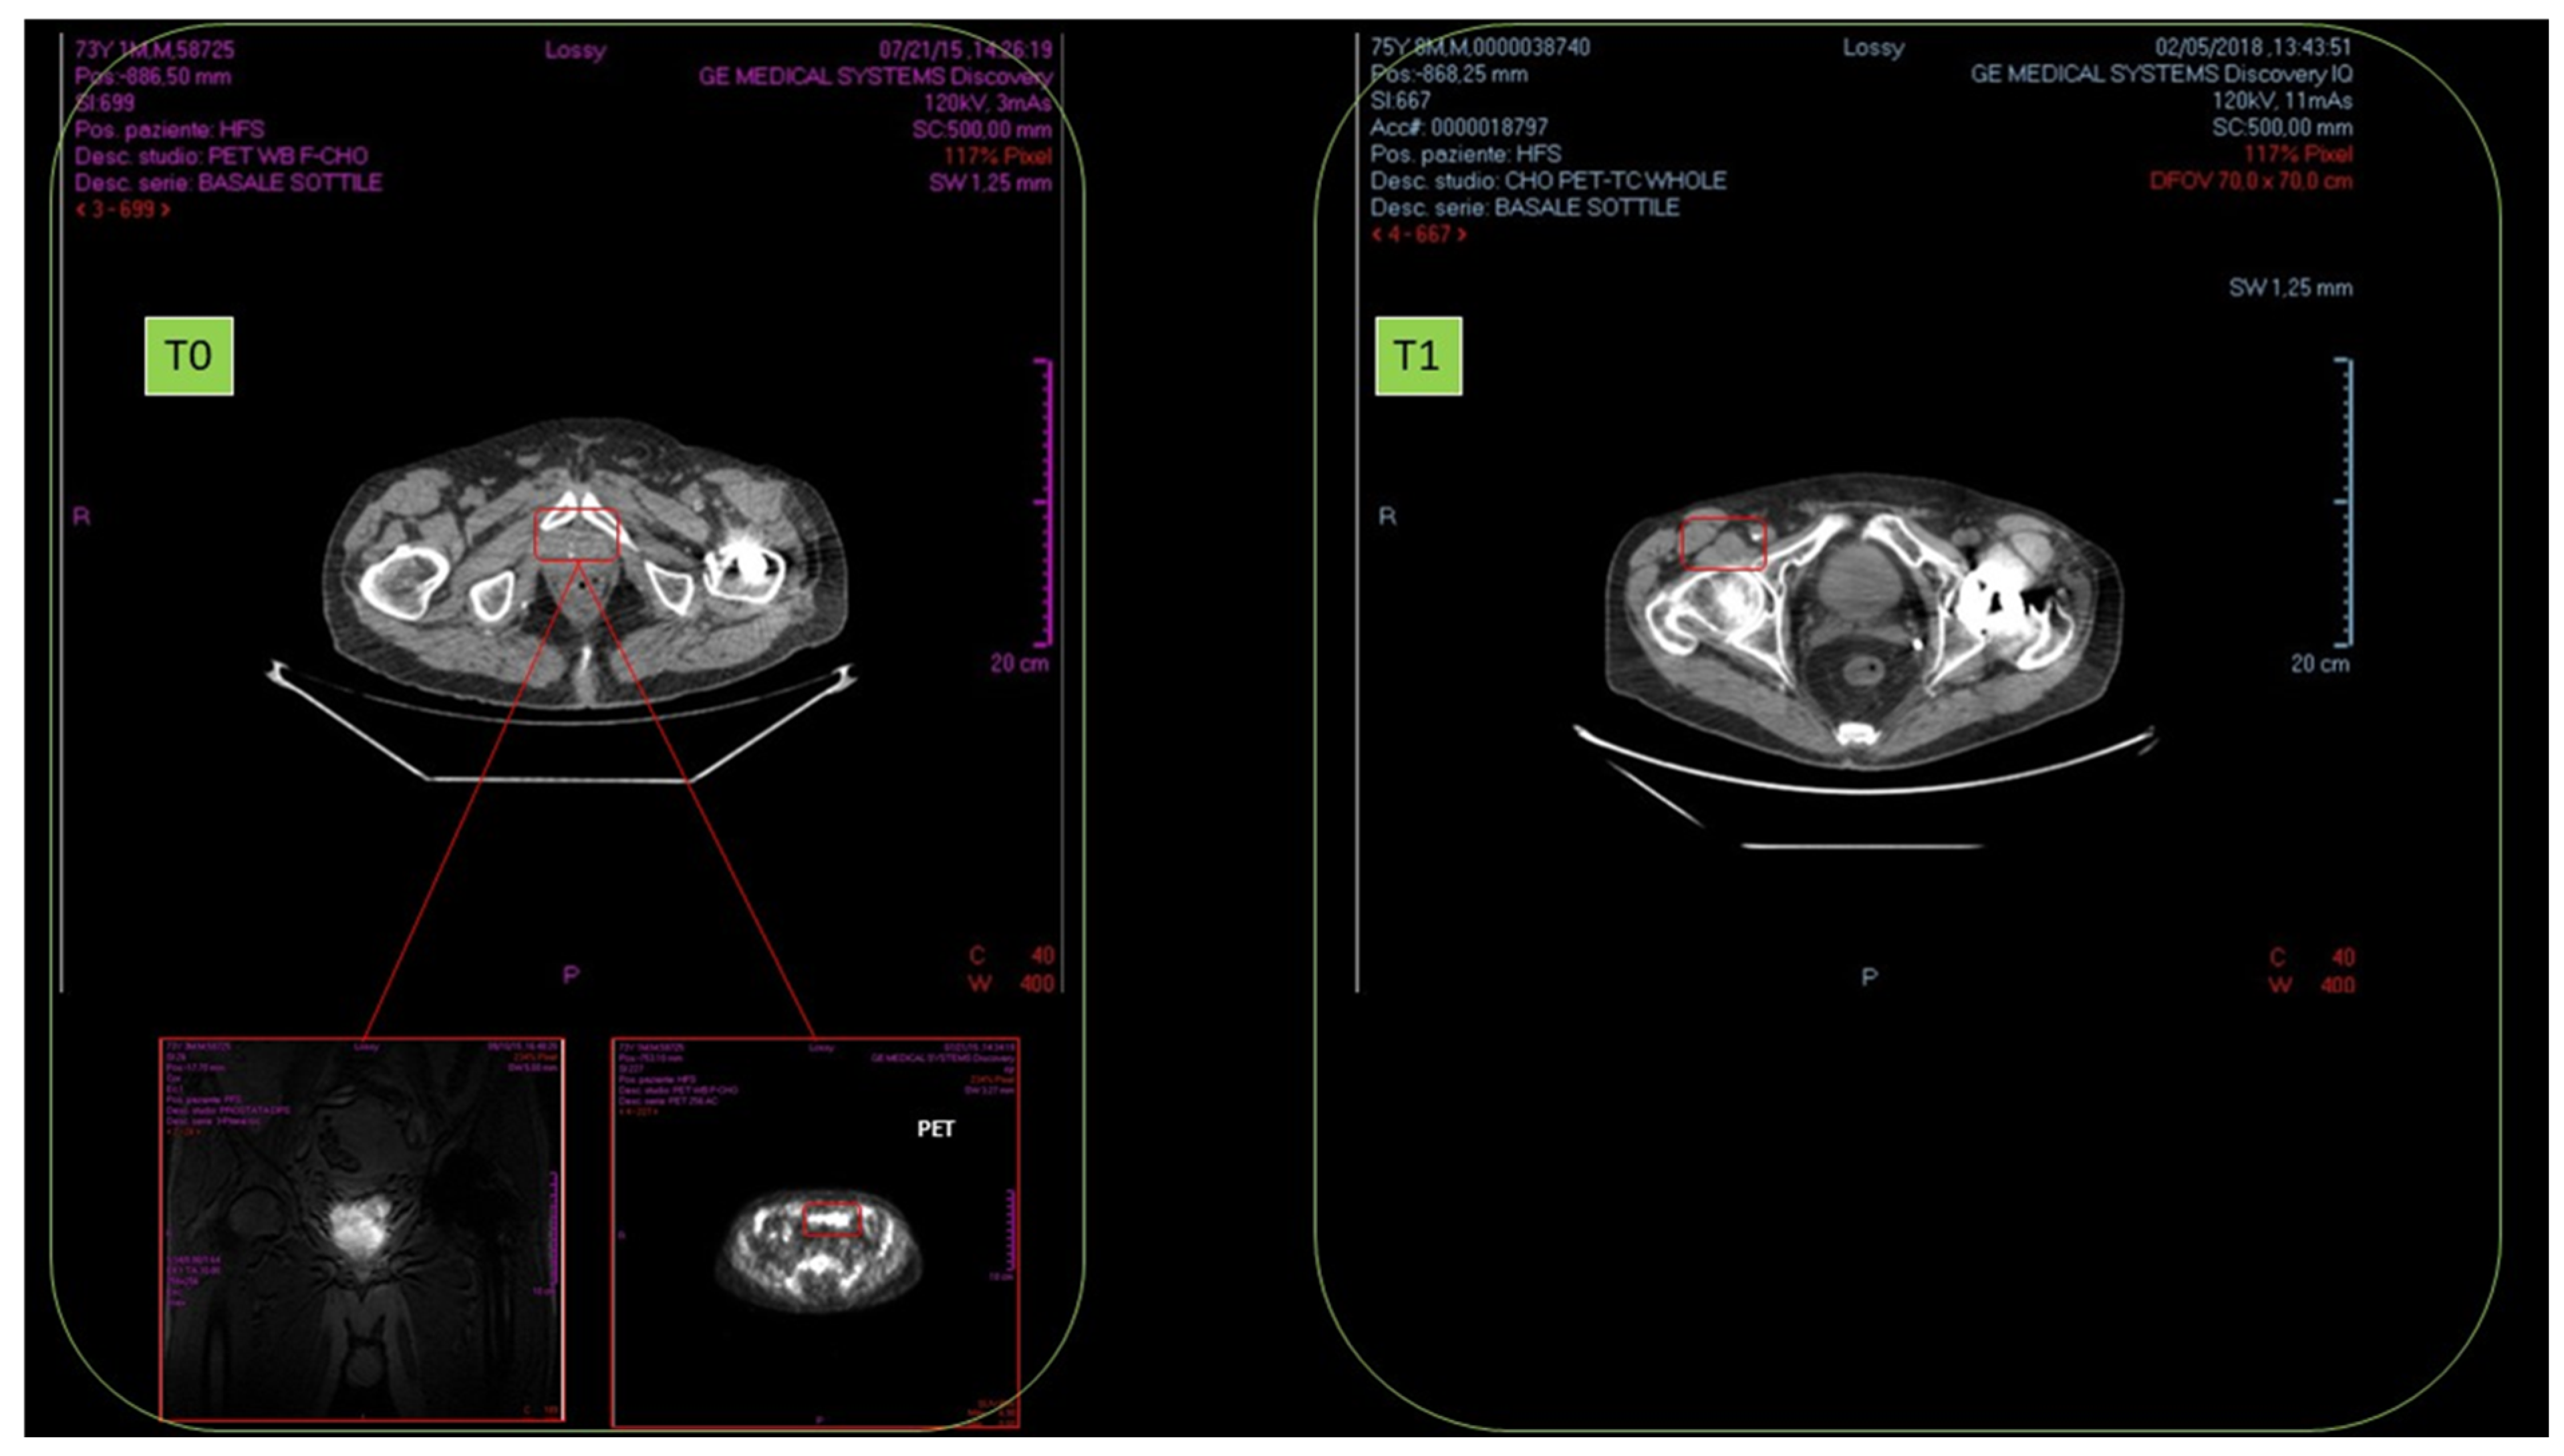

There was a 76-year-old male, affected by prostate cancer (adenocarcinoma), as confirmed by biopsy and histopathological examination (September 2015). No local or distant metastasis was detected. NMR revealed high metabolic rate, fast cell proliferation, and blood vessel proliferation. Biopsy detected severe inflammation of cancer mass and surrounding tissue. Intermediate malignancy: Gleason score was 6, and cancer dimension was 3.0 cm.

No results were observed in anti-hormonal therapy (November–December 2015). Standard radiotherapy regimen was of 40 sessions (January–March 2016). In October 2016, after radiotherapy, NMR detected cancer persistence with cell proliferation and remarkable blood vessel proliferation.

From January 2017, HOO oral treatment (12.5 mL twice a day for 18 months) was started. In February 2018, TAC and radioimaging demonstrated complete cancer disappearance (Figure 16).

No relapses were insofar detected (ongoing follow-up, 18 months).

No adverse effect related to the ozonized oil treatment was detected.

Figure 16. Disappearance of radioresistant prostate carcinoma (T0) after 1 year of HOO treatment (T1), as detected by nuclear magnetic resonance in a 76-year-old male patient.